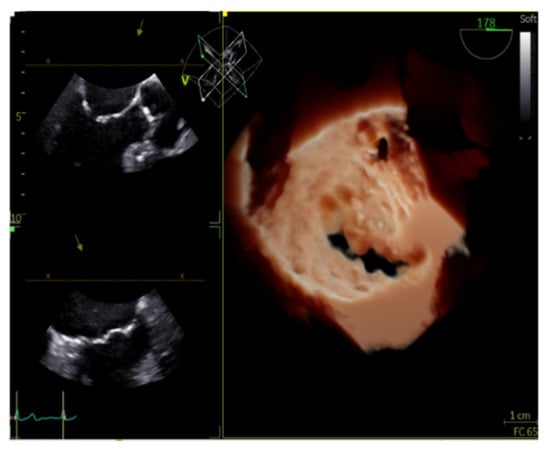

7. Fusion Imaging

The evaluation of cardiac function in real-time with increased spatial resolution has become critically important during transcatheter interventions and is gaining ground day by day as a mainstay in cardiac care with regard to treatments for structural heart disease. These procedures, while minimally invasive for patients, often have added degrees of patient-related and procedure-related complexity. Fluoroscopy has long been the cornerstone of interventional procedures due to the excellent device visualization and due to the fact that it provides real-time feedback. On the contrary, fluoroscopy offers poor characterization of non-radiopaque structures and provides only 2-D projections of important 3-D cardiac anatomy, lacking essential spatial resolution. Fusion imaging combines data from different imaging modalities, fluoroscopy, computed tomography, and echocardiography, in order to produce a fused image, video, or live streaming (Figure 14). With these methods, we have access to high-resolution detailed anatomic information from CT imaging combined with functional, real-time motion and flux information from echocardiography. The fusion of the pre-operative CT and the peri-procedural 4D-TEE provides us with an excellent visualization of both images in the same visual perspective on the echo screen in the catheterization laboratory [38,39,40,41,42].

Figure 14. CT Fusion image the display of co-aligned 4D TEE ultrasound and CT data.